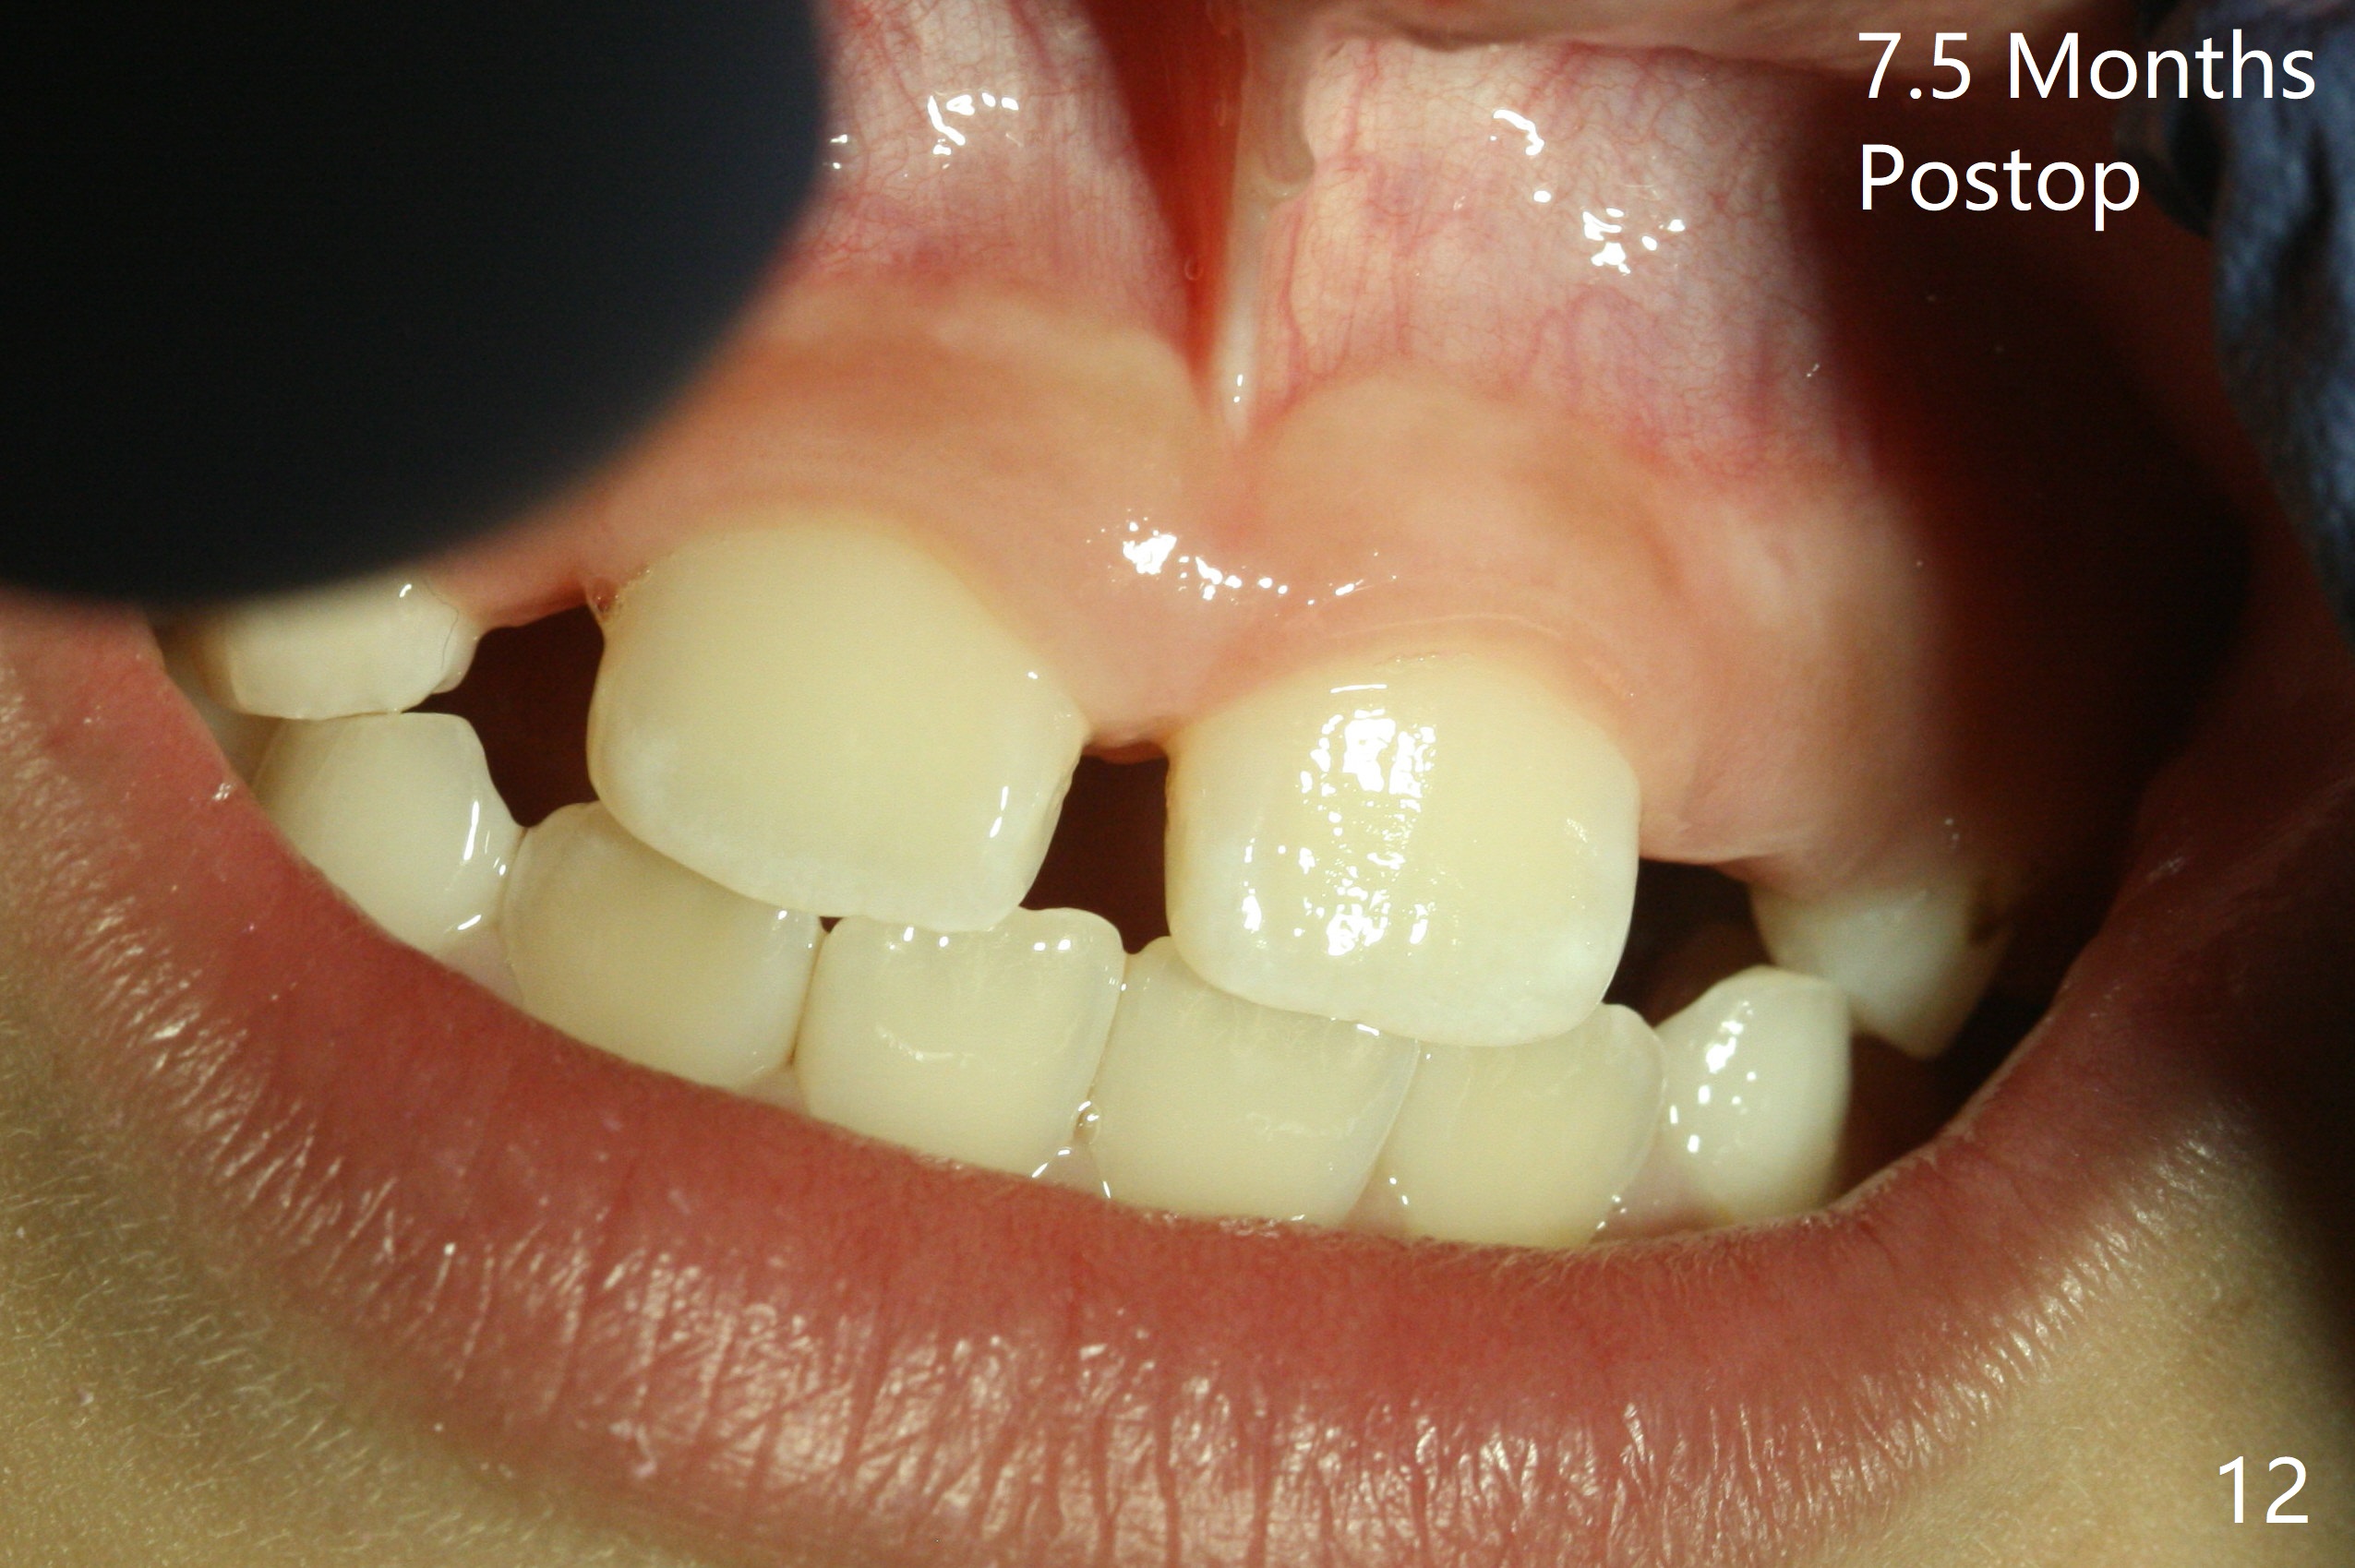

There is a large diastema between the upper central incisors (Fig.7). The left anterior palate is slightly elevated (Fig.8 *). In fact the cortex overlying the mesiodens (Fig. 9 *, 11 <) is to be removed with a surgical handpiece in order to extract the mesiodens (Fig.10). The left central shifts mesial in 7.5 months postop, whereas the right one remains in place (Fig.12). The tooth #7 is unerupted 1 year 4 months postop (Fig.13).